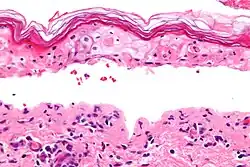

| Micrograph of confluent epidermal necrosis. H&E stain. | |